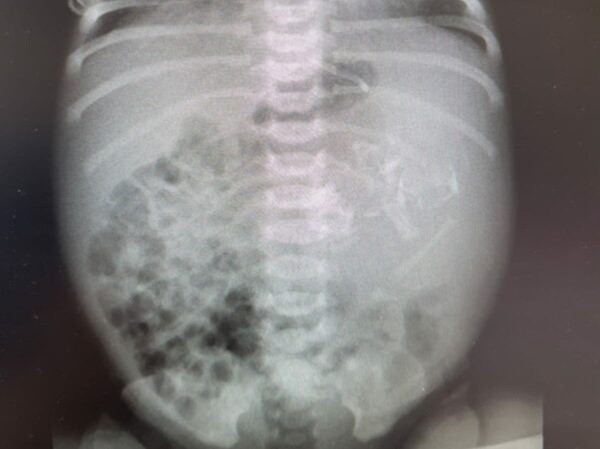

▲以色列一名女嬰胃裡出現不完全胚胎。(圖/翻攝阿蘇塔醫療中心)

阿蘇塔醫療中心(Assuta Medical Center)婦產科主任醫師葛洛柏斯(Omer Globus)表示,女嬰在媽媽懷孕末期產檢時,就被發現胃部增大,出生後接受超音波與X光檢查,才發現胃裡竟有胚胎。他說,「這是胎兒發育過程的一部分」,但本案例胚胎發育並不完全,與大眾想像中的胚胎可能不太一樣。